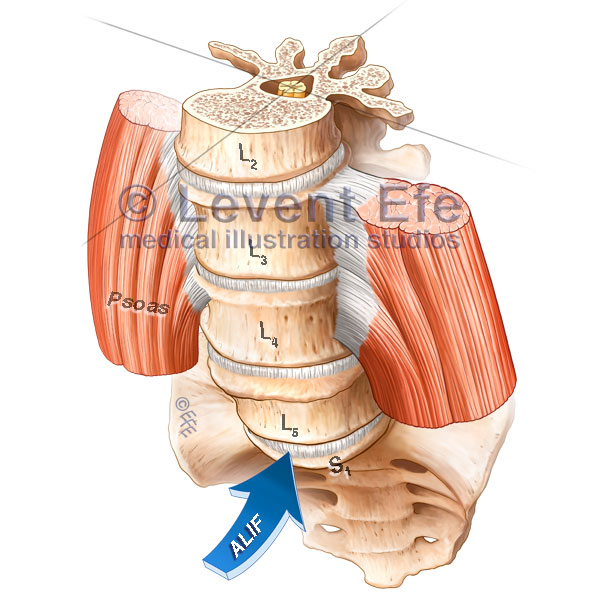

Amazon.com: Atlas of Image-Guided Spinal Procedures: Atlas, ALIF-Spine surgery Approaches | Dr. Efe's Medical Art Store,

ALIF-Spine surgery Approaches | Dr. Efe's Medical Art Store, Ahead of the curve: Surgery for scoliosis no longer so「脊椎脊髄の手術 = Illustrated Surgery of Spine & Spinal Cord 第2巻」戸山 芳昭 / 花北 順哉定価: ¥ 240002015年初版状態:カバーに少スレ、小口にヨゴレ、角にヨレありますが、通読に支障はありません。※画像で状態をご確認ください。※古本につき、過度に状態を気にされる方はご遠慮ください。#戸山芳昭 #戸山_芳昭 #花北順哉 #花北_順哉 #本 #自然/医療・薬学・健康